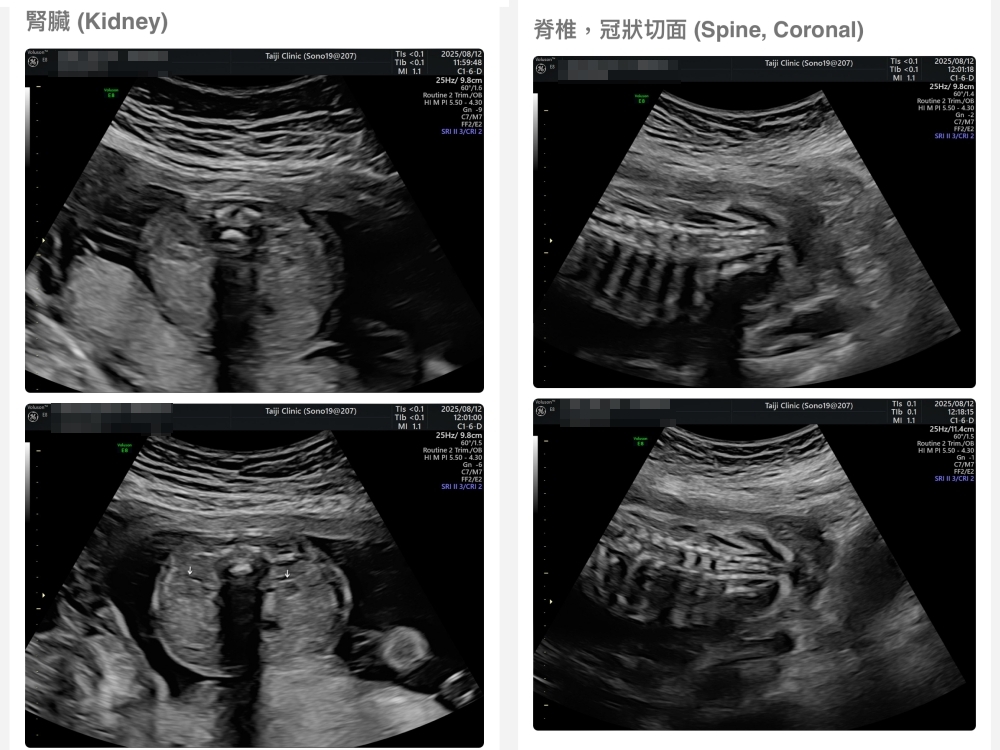

【台兒|高層次超音波|檢查結果】

▲離開診所後會收到MAIL,我們14:05離開,大約是16:45收到mail,裡面會有滿滿的超音波照片,紀錄的很詳細!也會提供紙本的報告,可以給日後產檢的醫師做參考👌